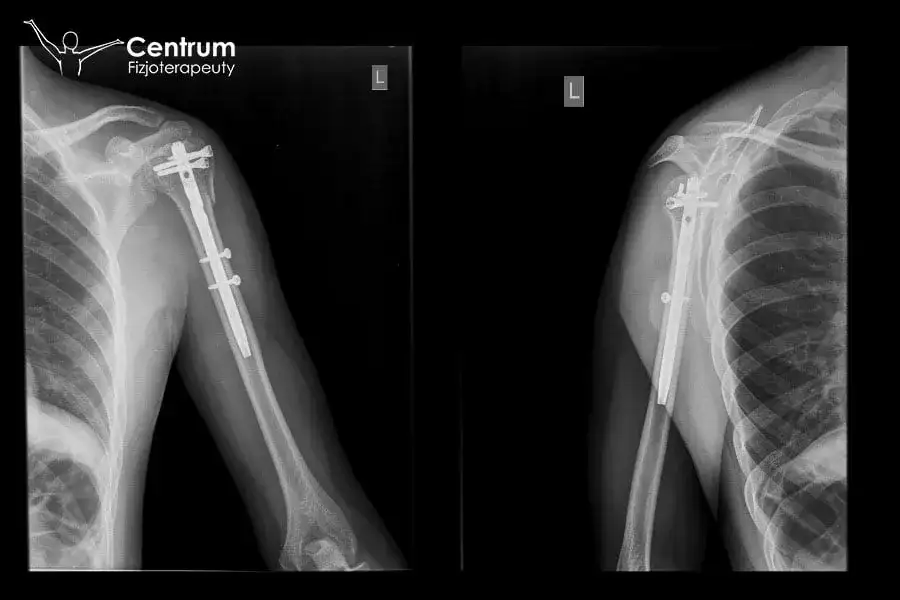

Rehabilitacja po złamaniu kości ramiennej: ile trwa i co wpływa na powrót do sprawności? Poznaj etapy, ćwiczenia i czynniki sukcesu. Sprawdź!